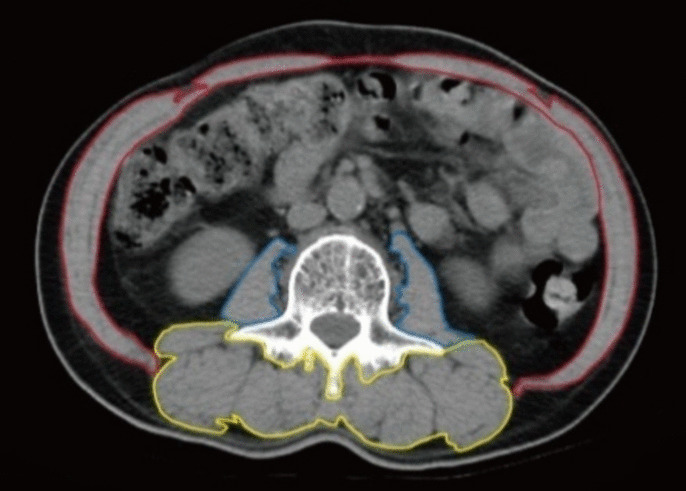

Methods: In this retrospective study, 387 non-metastatic CRC patients undergoing laparoscopic radical resection were categorized into a sarcopenic group and a non-sarcopenic group based on preoperative skeletal muscle index (SMI, cm2/m2). Logistic regression analysis was performed to identify independent predictors for postoperative complications.

Abstract Image